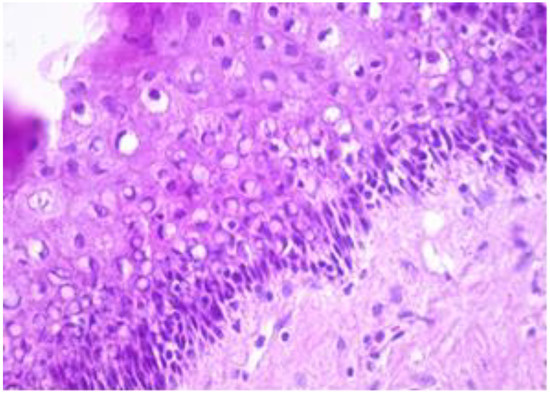

Other areas of the cyst are lined by stratified, flattened epithelium with focally outer fine, but distinct, granulated eosinophilic cytoplasm cells (Figure 5). The cyst’s epithelium, content and overlying exocervical epithelium are marked positive (Figure 6). The epithelium of the cyst is also marked as intensely positive (Figure 7). The myometrium presents islands of endometrial stromal and glandular structures within its thickness. In the endometrium, we are able to assess the ratio between the glandular structures and stroma and we notice that it is strongly modified in the gland’s favour. Para tubal, we see a cystic structure with amorphic, slightly eosinophilic content. This cystic formation is lined at the most intimate level by a single layer of cuboidal, cylindrical cells, sometimes presenting a flattened structure.

Figure 5. Other areas of the cyst are lined by a stratified, flattened epithelium with focally outer fine, but distinct, granulated eosinophilic cytoplasm cells (HE staining, 40×).